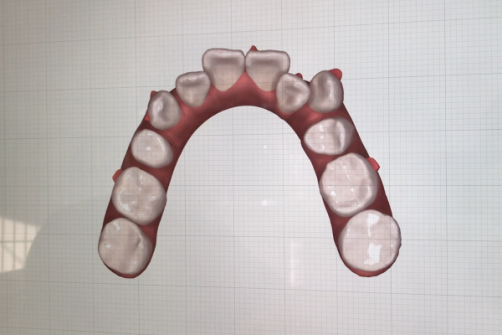

コンピューターを使って作製した透明なマウスピース型の矯正装置(アライナー)を段階的につけ替えていき、それにより歯列を矯正し、歯並びへと改善します。はじめに 治療開始から終了までのアライナーができあがってきます。マウスピース型矯正装置(インビザライン)の最大の特徴として「クリンチェック」というソフトがあります。3D のコンピュータ シュミレーション画像で、治療開始から完了までを目で見て確認することができます。

マウスピース型矯正装置(インビザライン)治療においては、クリンチェックというシミュレーションソフトを活用しております。

このクリンチェックの魅力は、治療前の現在の歯並びから治療後の歯並びを視覚化して患者様にご説明できる点にあります。

また、抜歯・非抜歯、全体矯正・部分矯正などそれぞれの治療パターンをシミュレーションすることが可能です。

アライナーとは、マウスピース型矯正装置で使用するマウスピース型の矯正装置のことです。ブラケット矯正は、曲げたワイヤーが戻ろうとする力を利用して歯を移動させます。対して、マウスピース型矯正装置は、 今の歯並びより少しだけ治療終了の歯並びに近いマウスピースを装着して歯に力をかけ、それを次々に付け替えていくことで歯を移動させます。治療終了までには数十個のマウスピース を使用することになります。